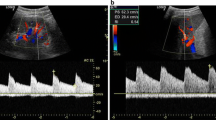

Assessment of renal resistance index. The examination of kidney and renal arteries is usually performed by an anterior approach by means of a convex ultrasound probe. The patient should be adequately prepared to avoid intestinal gases.

Nonetheless, it is possible to evaluate the renal resistance index (RRI) at the end of an echocardiogram also using the echocardiographic probe (Ciccone et al. 2014). With the patient in a lateral or sitting position, the scan images of the kidney are obtained from a posterior approach. The use of Color or Power Doppler helps to localize the vessels.

RRI slightly decreases from the hilum toward the renal cortex. Usually, pulsed Doppler volume sample is placed at the level of the segmental arteries. It is necessary to achieve the best alignment between the ultrasound beam and flow direction to record Doppler velocities maximizing waveforms gain and size, to obtain peak systolic velocity and end-diastolic velocity (Fig. 4). Three to five reproducible waveforms should be evaluated.

Renal resistance index calculation. Calculation of the renal resistance index. The renal arterial Doppler was performed using a 4 MHz probe with the patient in the sitting position and using a posterior approach to visualize the kidney. The course of the segmental arteries is visualized by color Doppler flow, and, at the middle tract level of the best one visualized, pulsed wave Doppler is performed. Peak systolic velocity and end-diastolic velocity are used to calculate the renal arterial resistance index according to Pourcelot formula